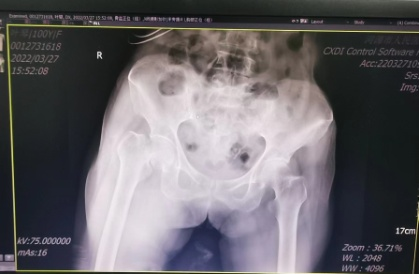

3月29日,家住河源连平的老寿星叶婆婆在家中不慎跌倒,当时就感觉右髋部疼痛、右下肢活动障碍。在当地卫生院就诊后,行X光片检查提示“右股骨颈骨折”,鉴于患者年龄大,手术风险高,患者家属遂要求转诊至我院进行进一步治疗。

术前骨盆正位片